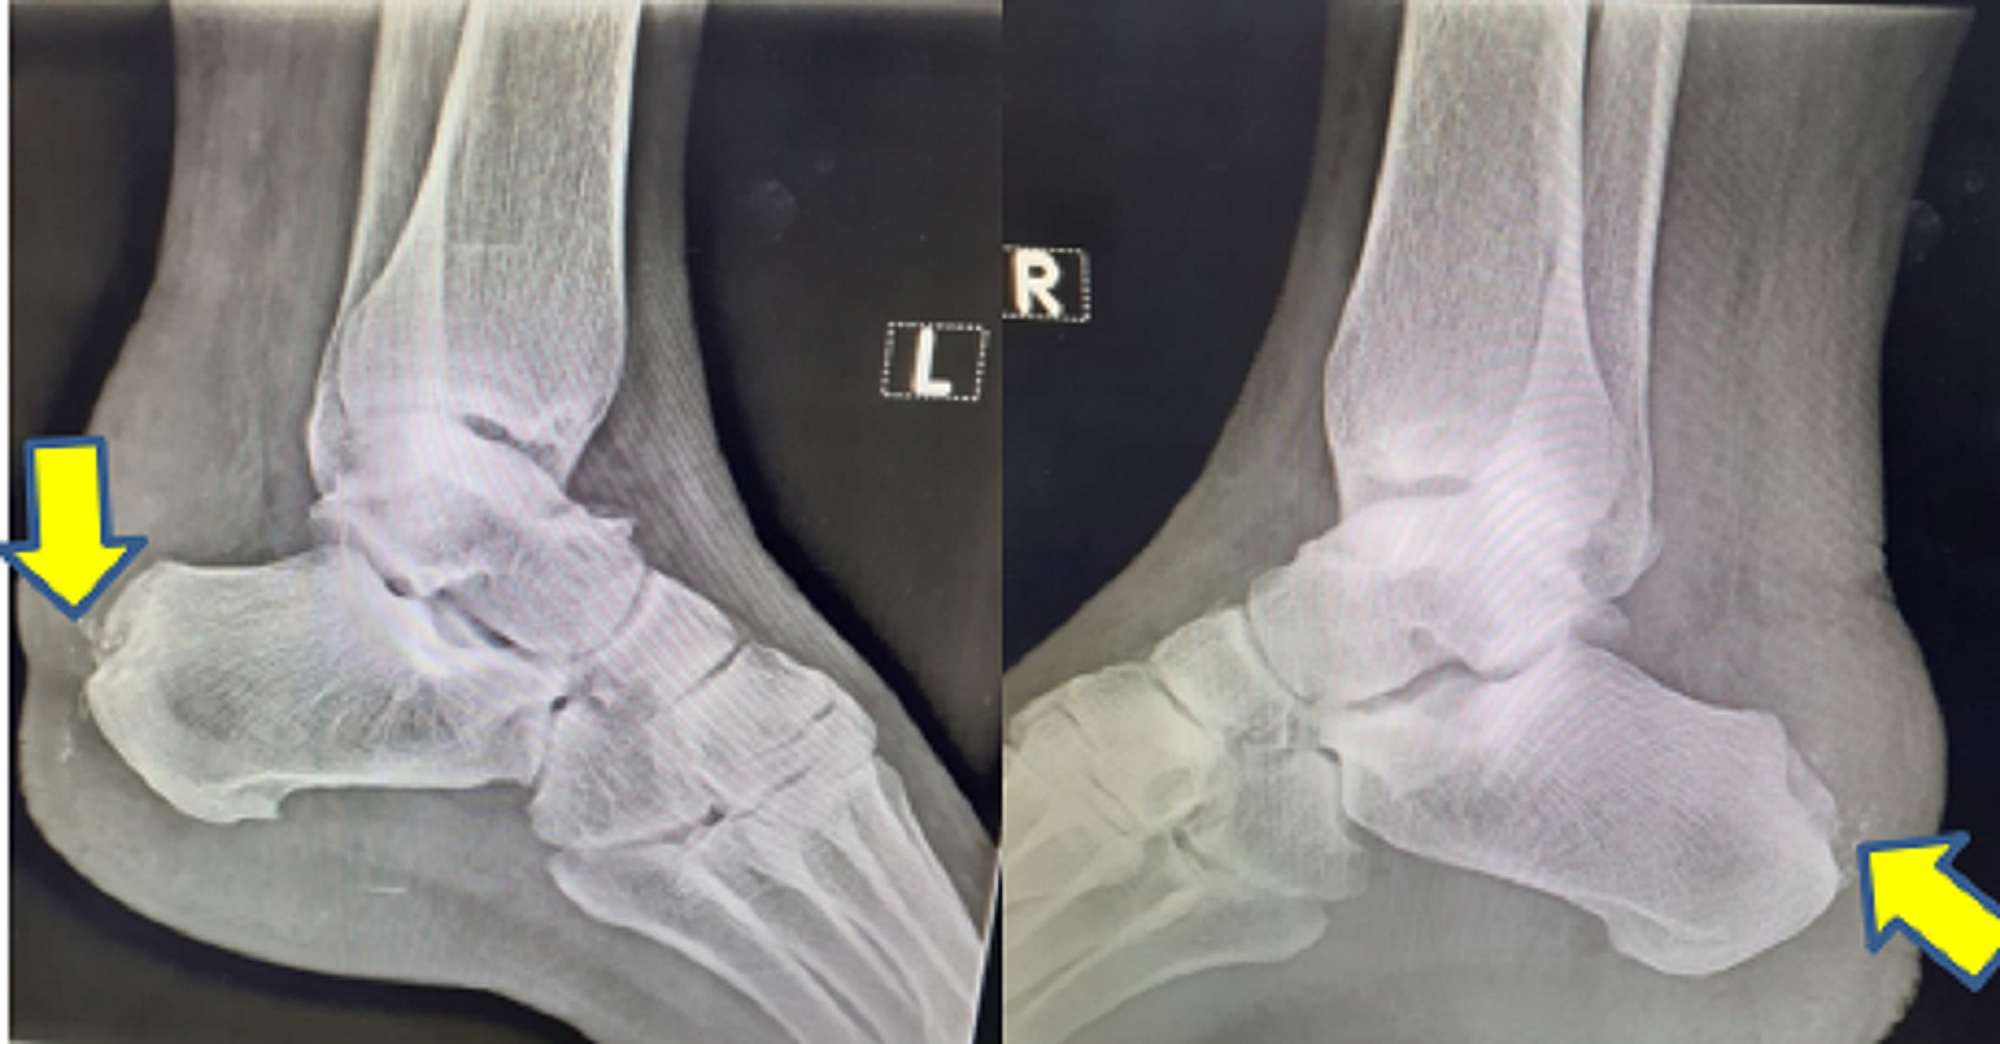

Haglund deformity / Pump Bump / Bauer Bump / Mulholland deformity Radiology www Pump Bump Symptoms Someone with pump bump will have a hard lump over the back of their heel, usually level with the top of their. A noticeable bump on the back of the heel; Haglund’s deformity is a bony ridge or bump that appears on the back of the heel bone, where the achilles tendon attaches to the heel. What does pump bump. Pump Bump Symptoms.

Cureus Mulholland Deformity With Pump Bump Pump Bump Symptoms What does pump bump look like? Haglund’s deformity can occur in one or both feet. Hence, the common name for this. Symptoms the primary symptoms of haglund's deformity are an enlarged bony prominence on the back of the heel and heel pain. Haglund’s deformity is a bony ridge or bump that appears on the back of the heel bone, where. Pump Bump Symptoms.

(PDF) Mulholland Deformity With Pump Bump Pump Bump Symptoms When that bony enlargement rubs against an external object (in most cases, the heel counter of a shoe; What does pump bump look like? Haglund's deformity is a bony bump where your achilles tendon attaches at the back of your heel bone. Haglund’s deformity is a bony ridge or bump that appears on the back of the heel bone, where. Pump Bump Symptoms.

Haglund deformity, also known as a pump bump, Bauer bump, or Mulholland deformity, is defined as Pump Bump Symptoms Symptoms the primary symptoms of haglund's deformity are an enlarged bony prominence on the back of the heel and heel pain. When that bony enlargement rubs against an external object (in most cases, the heel counter of a shoe; Also known as a pump bump, it is usually caused by shoes. What does pump bump look like? Haglund's deformity is. Pump Bump Symptoms.